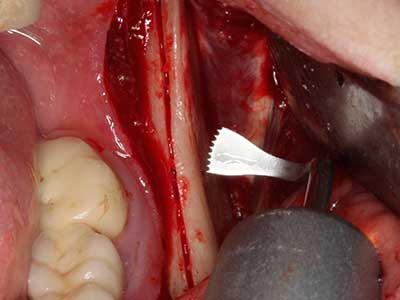

Knochengewebe ist nicht nur rein mineralisch, sondern auch in wesentlichen Anteilen aus Kollagenfasern aufgebaut. Dies gewährleistet neben einer guten Druckfestigkeit eine gewisse Flexibilität, welche für die Durchführung von Augmentationen genutzt werden kann. Bei der klassischen Expansionsplastik im Sinne eines Bone Splittings wird der atrophierte Kieferkamm in seiner Längsachse gespalten und nach Erreichen einer ausreichenden Osteotomietiefe vorsichtig aufgedehnt (Abb. 13-16), idealerweise ohne den Kiefer wesentlich zu deperiostieren (Brugnami, Caiazzo et al. 2014, Stricker, Fleiner et al. 2014). Bewährt haben sich Schrauben- und Plattensysteme mit zunehmender Expansionsdistanz, um die beiden Knochenlamellen unterhalb der Bruchschwelle voneinander zu distanzieren. In der Regel werden Restknochenbreiten von mindestens 3-4 mm gefordert (Chiapasco, Zaniboni et al. 2006), um eine ausreichende Flexibilität und knöcherne Bedeckung der einzubringenden Implantate zu gewährleisten. Ggf. kann eine ein- oder beidseitige vertikale Entlastungsosteotomie die Flexibilität verbessern. Als Alternative zur klassischen Technik wurde eine Kombination mit weiteren augmentativen Techniken vor allem auf der bukkalen Seite beschrieben.

Mittels Piezosägen erfolgt die Anlage des Splittings besonders schonend und ohne wesentliche Dimensionsverluste, so dass sich keine signifikanten Unterschiede von Implantaten im gesplitteten Kiefer im Vergleich zum nicht defizitären Alveolarkamm gezeigt haben (Chiapasco, Zaniboni et al. 2006, Danza, Guidi et al. 2009). Gerade beim lokal begrenzten und tiefen Splitting ist jedoch stets auf eine ausreichende Wasserkühlung zu achten, um thermische Belastungen in den apikalen Osteotomiebereichen zu vermeiden.

Abb. 13: Bei diesem 52-jährigen Patienten ist bei 4 mm UK-Restknochenbreite während des Bone Splittings auf eine ausreichende Wasserkühlung zu achten.